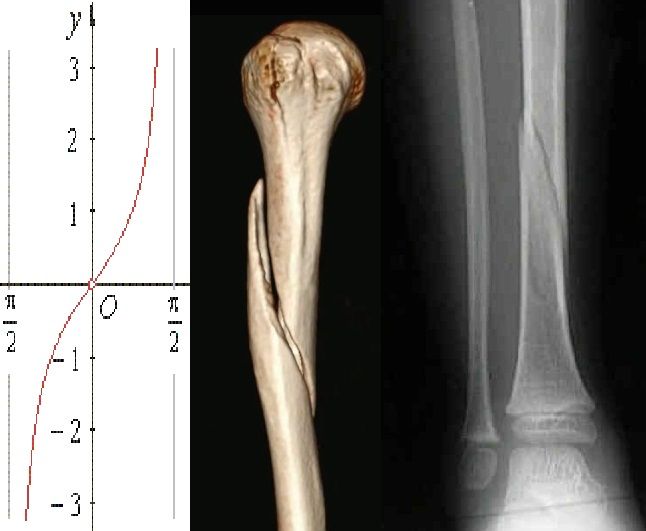

Spiral fractures

Time to get a little bit more complex. A spiral fracture is... nasty! Imaging your bone being held at both ends then twisted till it breaks... well that's a spiral fracture. The pattern we see in 3D is somewhat of a corkscrew style break, but in the 2D of an X-Ray this can be hard to pick up. What we see instead is a pattern that look s a little bit like a tan function...